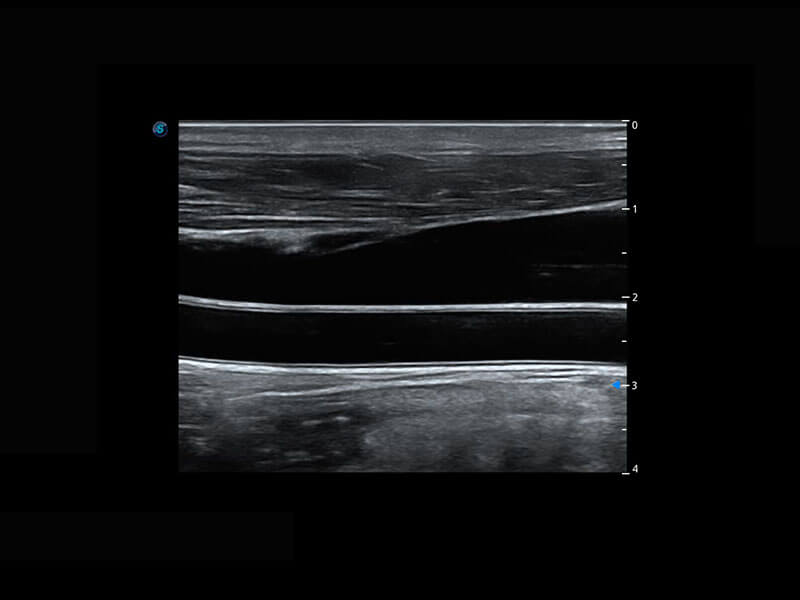

P60优异的图像质量搭载专科探头,在妇科基础疾病的诊断、卵泡生长的监测、输卵管通畅情况的判别等方面为您提供生殖应用方案。

腔内妇科-宫腔分离

腔内妇科-卵巢